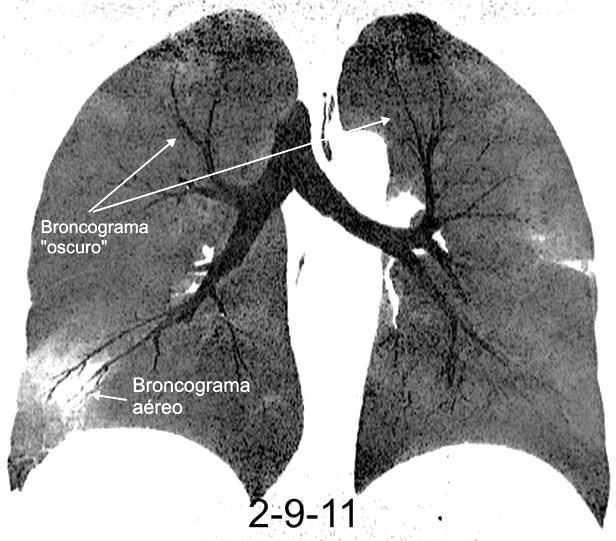

BRONCOGRAMA “OSCURO”

SIGNO DEL (dark bronchus sign)

Visualización de un bronquio más oscuro que el parénquima que le rodea.

Se ha descrito en casos de neumonía por Pneumocystis jirovecii

Yadav P et al. The 'dark bronchus' sign: HRCT diagnosis of Pneumocystis carinii pneumonia. Ann Thorac Med. 2007

Gruden JF et al . High-resolution CT in the evaluation of clinically suspected Pneumocystis carinii pneumonia in AIDS patients w ith normal, equivocal or nonspecific radiographic findings. AJR 1997

MiniP